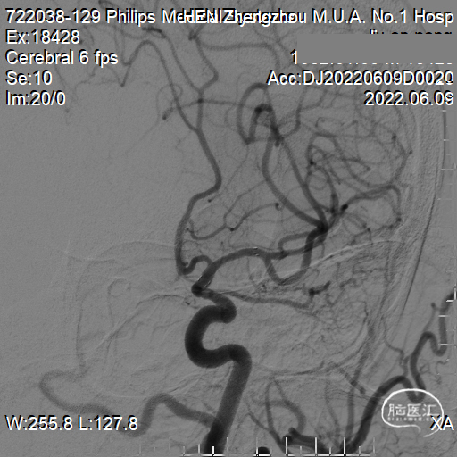

DSA提示:右侧大脑中动脉M1起始部极重度狭窄、次全闭塞,狭窄远端M1段管径约2.1mm,近端颈内动脉末端管径约3.3mm;M2段主干中度狭窄,分水岭下移;颈内动脉入路非常迂曲。

予缓慢充盈球囊至10atm,透视下观察球囊已充盈饱满,静待20秒,缓慢泄压球囊,造影提示局部管腔毛糙并粗细不均,担心弹性回缩基础上伴夹层形成。

借助支架输送系统回送支架导管至支架尾端顶住再撤出支架系统,保留微导丝,观察20分钟,见血流通畅,撤出微导丝,回撤导引导管和中间导管,正侧位减影和非减影像造影提示大脑中动脉血流通畅良好,支架远近端均匀贴壁,分水岭恢复正常。

该病例的血管条件较差,近端血管严重迂曲的同时靶病变部位重度狭窄为手术医生带来了巨大的挑战。术中影像能够明显看出术者手术技巧娴熟,同时术后影像也看到前向血流明显改善接近完美。